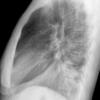

Round pneumonia

different case

Date: 11/28/2009

Views: 6361